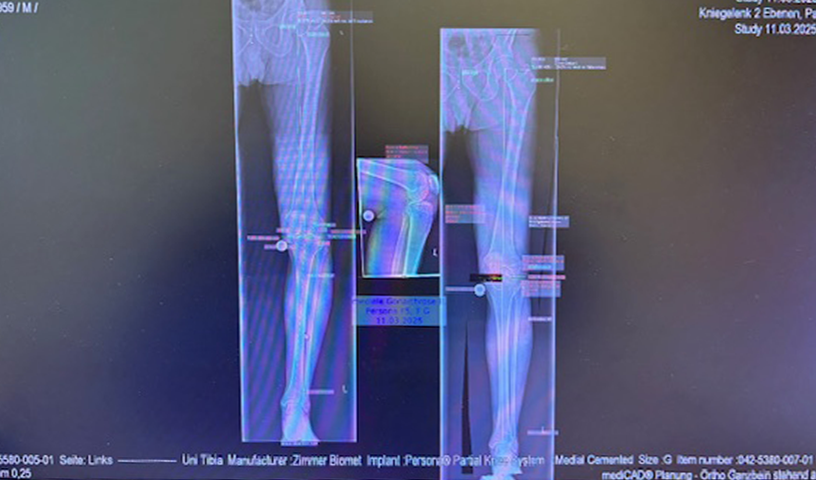

Ο προεγχειρητικός ψηφιακός σχεδιασμός

Πραγματοποιήθηκε απεικόνιση και ψηφιακός σχεδιασμός της επέμβασης, ώστε να προσδιοριστεί με ακρίβεια το μέγεθος και η θέση των προθέσεων. Ο στόχος ήταν να αποκατασταθεί η φυσιολογική μηχανική του γόνατος, διατηρώντας ανέπαφα τα υγιή τμήματα της άρθρωσης, τους συνδέσμους και τους γύρω μυς.